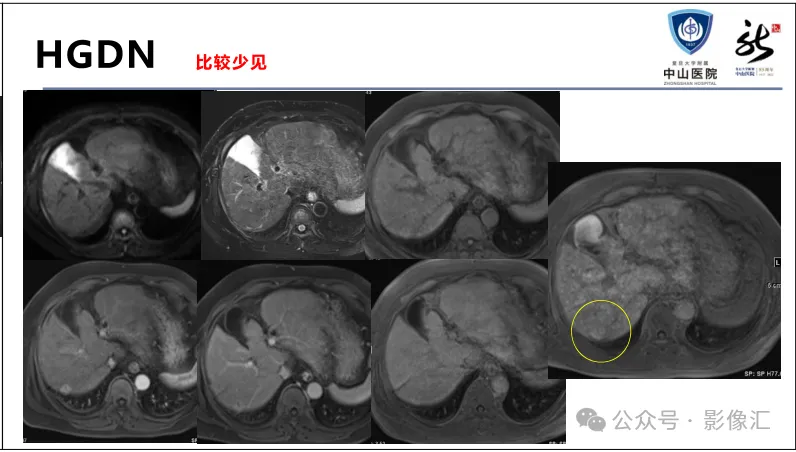

>【精品课件】如何正确判读肝胆特异性对比剂增强图像?

肝胆特异性对比剂增强肝胆图像判读方法与策略,课件来源于网络,作者复旦大学附属中山医院放射科饶圣祥教授。